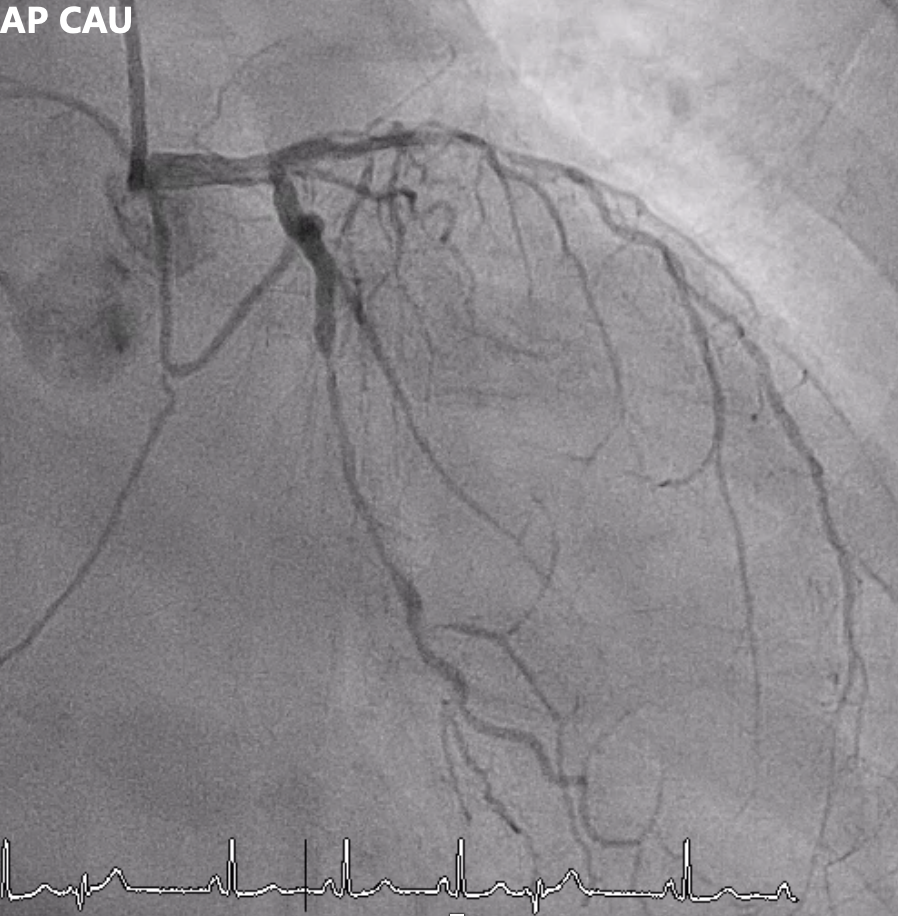

Angiography showed multivessel atherosclerosis with the LAD being the most critical lesion. The mid LAD had tubular eccentric 70–80% stenosis with a Medina (0,1,1) bifurcation and a mid-segment CTO (~2 cm, blunt end). DB1 had 70–80% ostial stenosis with 50–70% diffuse disease, and DB2 had a short CTO with distal collateral flow from DB1. Other vessels had non-critical or moderate diffuse disease.

Left AP CAU.mp4